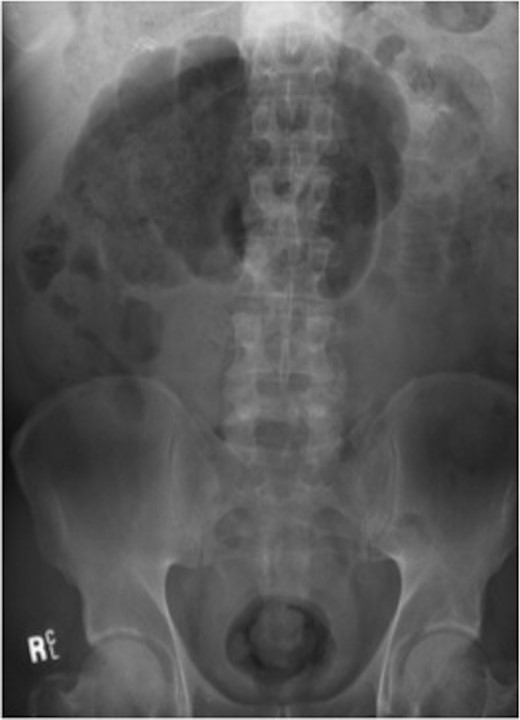

Haemoglobin was 12.6 g/dl and a WCC of 8.3 × 109/l. Other remarkable laboratory tests included a CRP of 19 mg/l. Urinalysis was normal. The AXR revealed a grossly distended large bowel. A CT scan of the abdomen revealed that the rectum, sigmoid and descending colon were collapsed with an apparent calibre change within the transverse colon with no mass lesion (Fig. 3).

CT of the abdomen (Case 2) showing a calibre change within the transverse colon with no mass lesion.